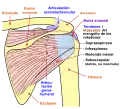

Músculos

Los siguientes músculos se insertan en el omóplato:

| Músculo | Dirección | Región |

| Pectoral menor | Inserción | Apófisis coracoides |

| Coracobraquial | Origen | Apófisis coracoides |

| Serrato anterior | Inserción | Borde medial |

| Tríceps braquial (cabeza larga) | Origen | Tubérculo infraglenoideo |

| Bíceps braquial (cabeza corta) | Origen | Apófisis coracoides |

| Bíceps braquial (cabeza larga) | Origen | Tubérculo supraglenoideo |

| Subescapular | Origen | Fosa subescapular |

| Romboides mayor | Inserción | Borde medial |

| Romboides menor | Inserción | Borde medial |

| Músculo elevador de la escápula | Inserción | Borde medial |

| Trapecio | Inserción | Espina de la escápula |

| Deltoides | Origen | Espina de la escápula |

| Supraespinoso | Origen | Fosa supraespinosa |

| Infraespinoso | Origen | Fosa infraespinosa |

| Redondo menor | Origen | Borde lateral |

| Redondo mayor | Origen | Borde lateral |

| Dorsal ancho (unas pocas fibras) | Origen | Ángulo inferior |

| Omohioideo | Origen | Borde superior |